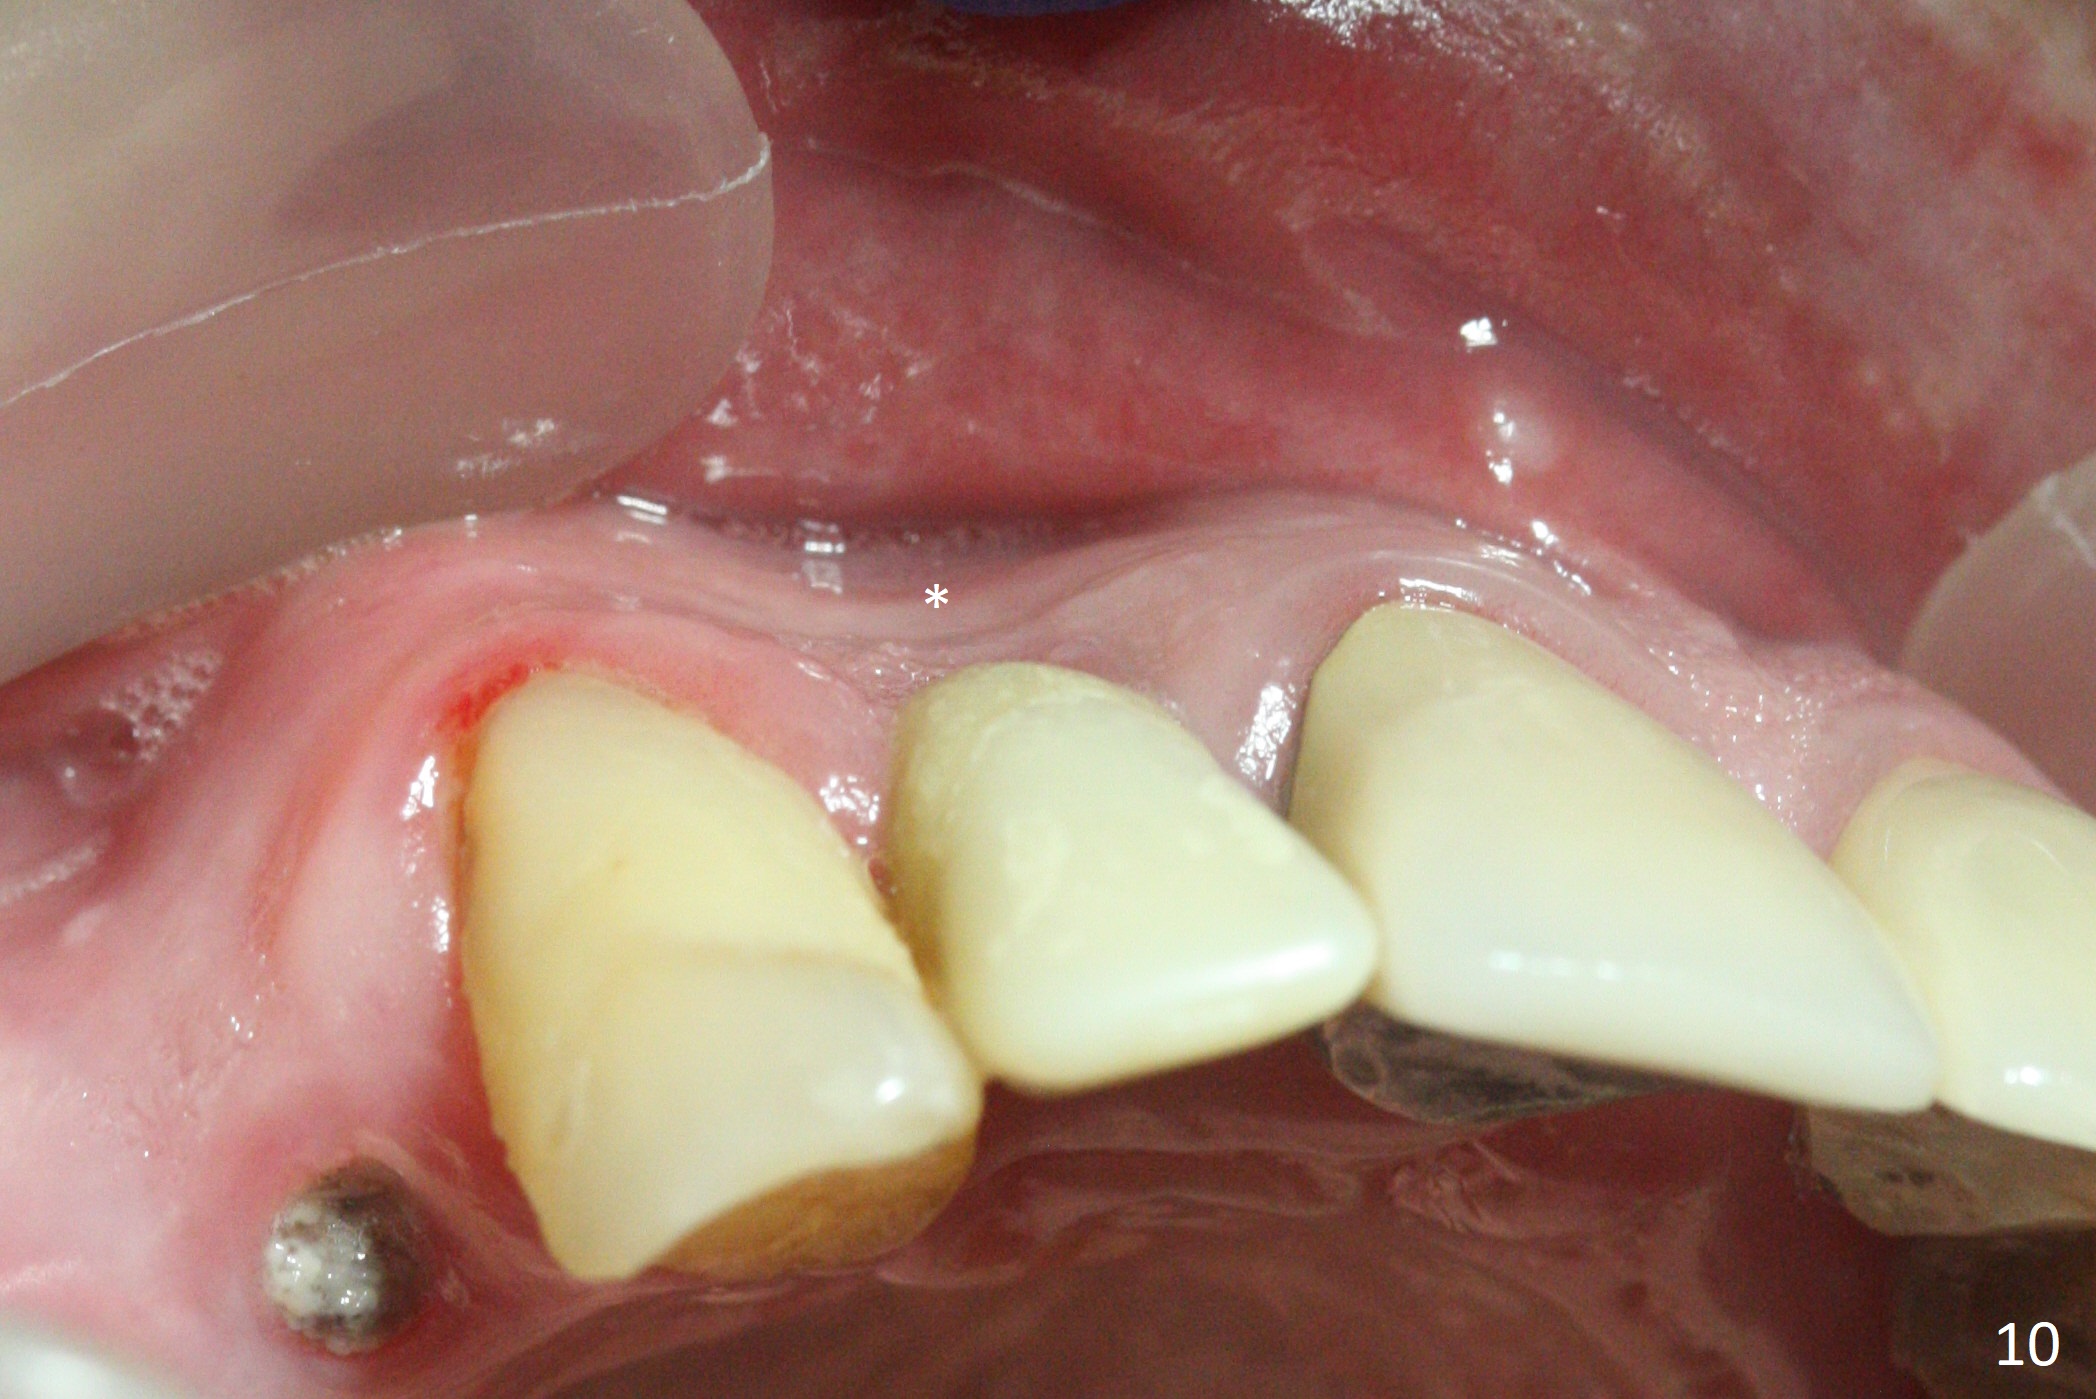

The gingiva adapts well to the provisional 1 week postop (Fig.8). The buccal gingiva remains recessive and the buccal plate is concave 5.5 months postop (Fig.9-11). It appears that the coronal portion of the buccal plate is resorbed 12 months postop (6 months post cementation, Fig.12 >). Socket shield or smaller diameter implant should have been done to avoid bone loss. Reanalysis of CBCT reveals that implantation apparently increases the bone width and that the buccal plate resorption is not so severe (Fig.13,14 (>: coronal end of the buccal plate)). Panoramic X-ray is taken 2 year 5 month post cementation.